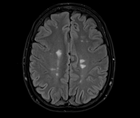

Monitoring Multiple Sclerosis: The Role of Serum Neurofilament Light Chain Levels

NeuroFrontiersMonitoring Multiple Sclerosis: The Role of Serum Neurofilament Light Chain Levels